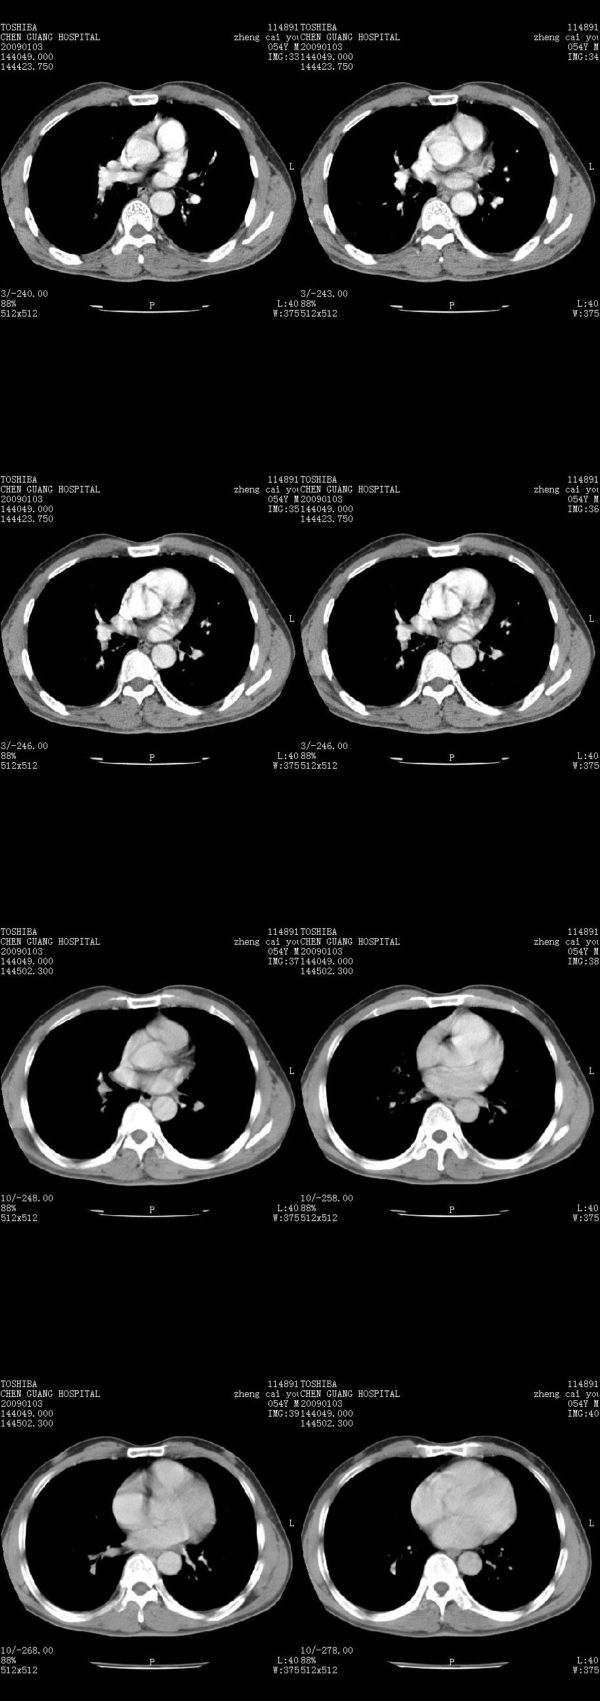

男,54岁,右侧胸部疼痛,平时吸烟,有抽烟后咳嗽咯痰史。昨天没把xiphoid软件吃懂,所以没把纵隔窗图像处理出来!请各位老师帮忙看一下右肺门有没有问题?谢谢!!!!!!!!!!

右肺上叶后段近气管旁仍可见一结节灶,不除外为肿大的淋巴结影。

我同学讲红线部分强化不好,感觉不是很舒服,这是什么道理?

我同学讲红线部分强化不好,感觉不是很舒服,应该 是软组织间隙,不是一个孤立的病灶。

气管前腔静脉后似见增大淋巴结影,肺门区未见明显肿块影。肺窗示右肺中叶外侧段透亮度增高,可过一段时间再查一下对比一下,毕竟是自己的至亲,又有条件,辐射就顾不得了。

也觉得还好吧,只是右下肺动脉显粗了点,纵膈有钙化淋巴结,再有肺窗就更好了

各位老师:奇静脉增宽,肺上未见明显实变,这还需注意观察些什么?????

右侧肺门影增大,不除外增大淋巴结可能